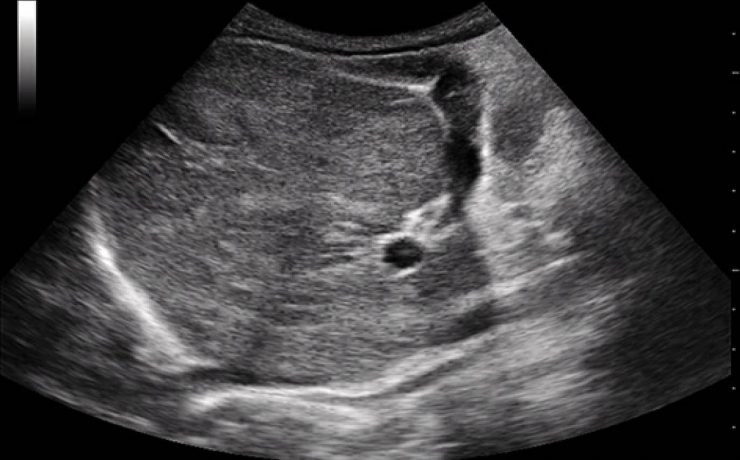

Ultrasonografía aplicada en medicina crítica

La introducción de la ultrasonografía en las Unidades de Cuidados Intensivos se deriva de la congregación de varios factores, como es la tecnología y las especialidades médicas afines al área de cuidados intensivos, con la finalidad de proveer la mejor atención al paciente grave. El primer aparato de ultrasonido se